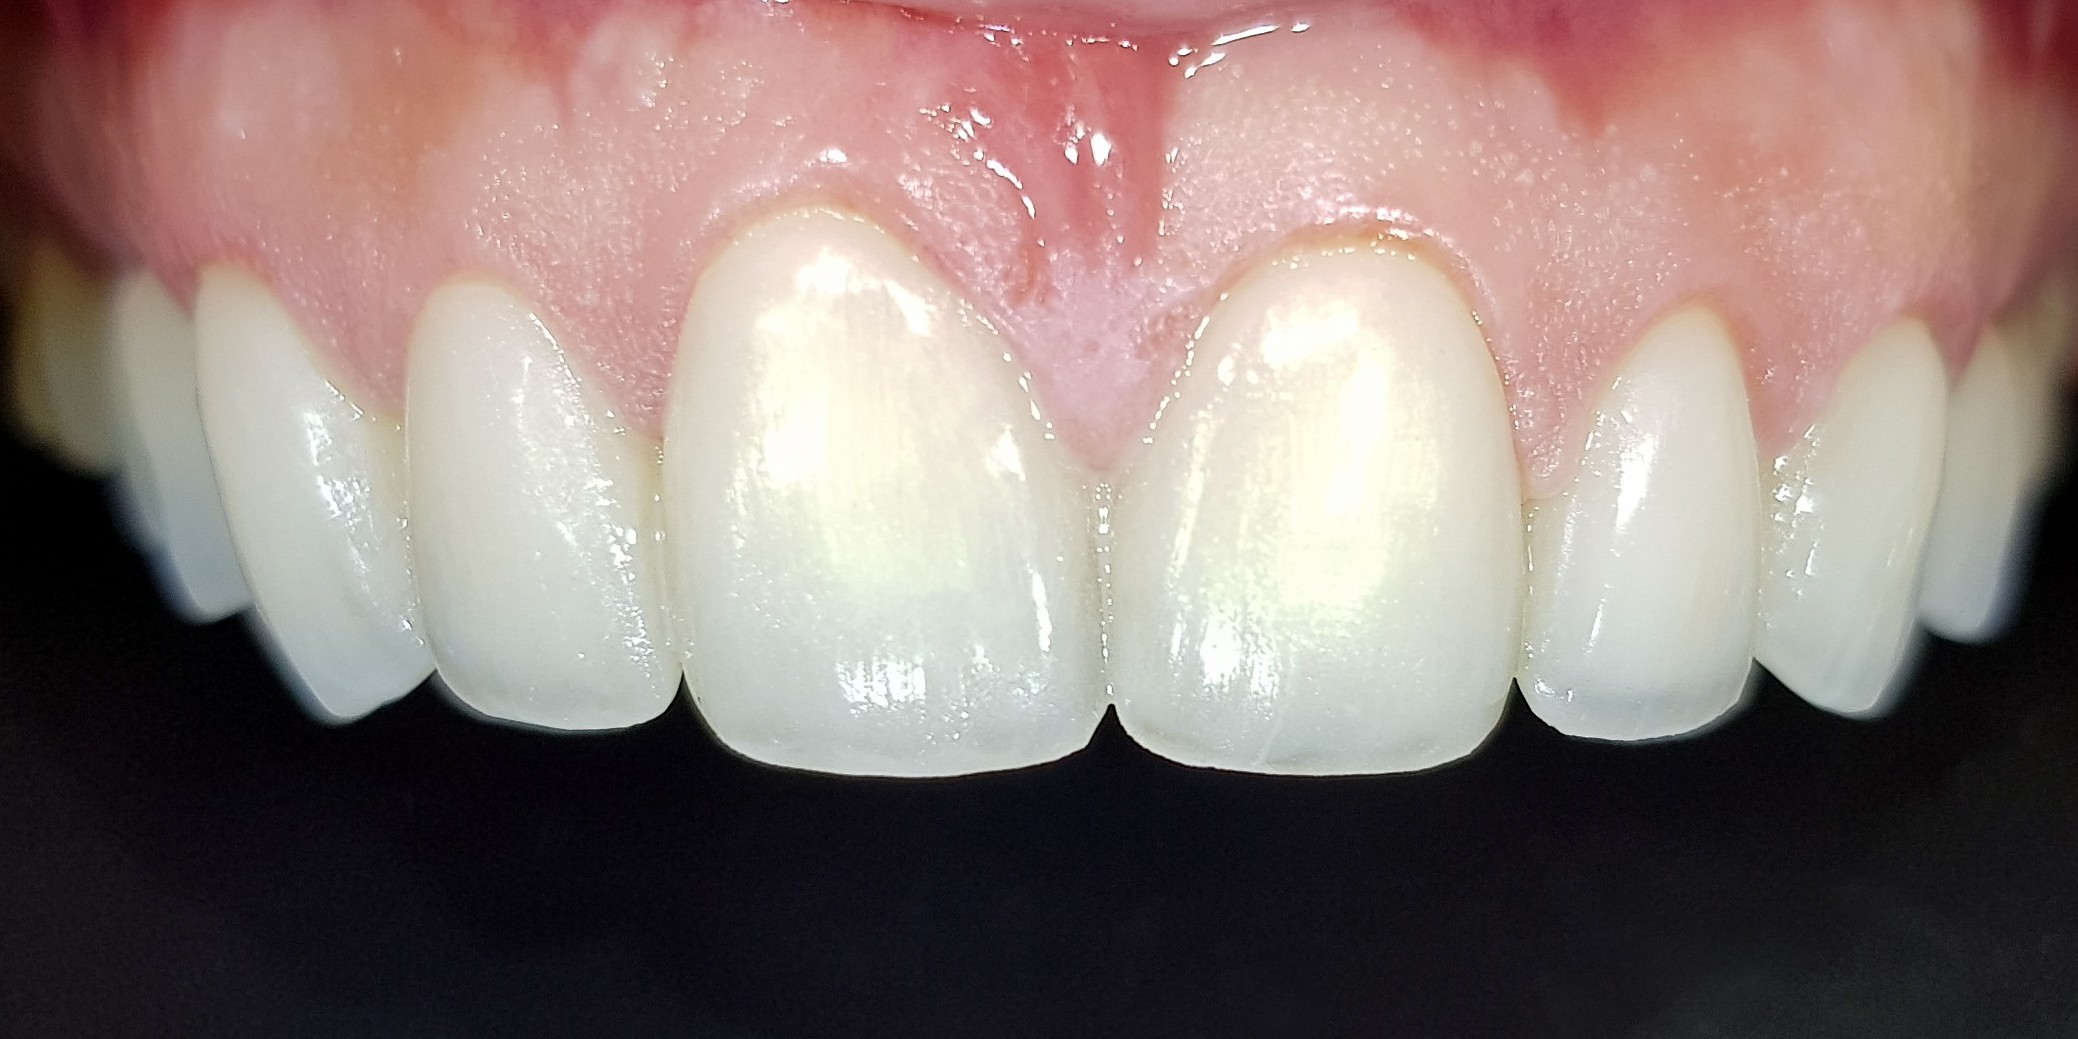

Bonding porcelain veneers, or as they go by their foreign name – laminate veneers, requires a lot of technical and medical skill, a lot of experience, perfectionism and an artistic eye. The transition area between the veneers and the gums is where millions of bacteria accumulate, causing gingivitis, bleedings and pain. The gums look swollen and unsightly. It is imperative to maintain good gum health to get a natural-looking and beautiful result. The goal is to achieve a beautiful and glamorous smile without letting others see that we have applied porcelain veneers. That is why one must not compromise when choosing a dentist.A cost-based compromise almost always leads to double work and double costs. The first time, people pay a low price, and the second time, they pay the right price to replace the porcelain veneers. A natural, healthy, white and beautiful smile is Dr. Gilad Fiskus’s signature.